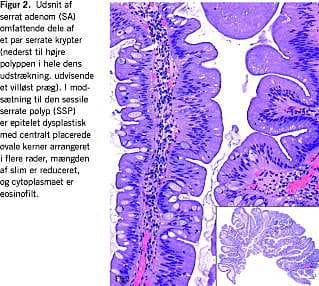

Serrate, hyperplastiske - og hyperplasilignende, kolorektale polypper ...